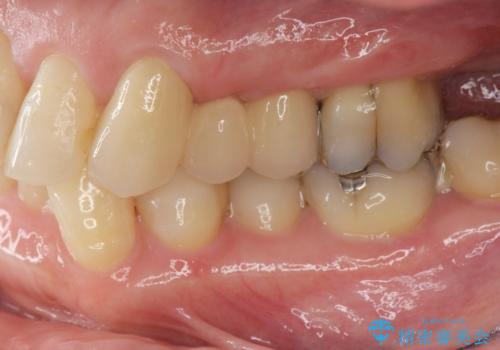

小矯正を伴う臼歯部ブリッジ治療

- 左上の歯の喪失し噛みにくいことの改善、歯を入れたいと希望され来院されました。

インプラント治療を行うには隙間が狭すぎるためブリッジか入れ歯をご提案したところ、取り外しの必要な入れ歯は希望されずブリッジを用いて機能・審美性の改善を行っていくこととなりました。

ブリッジの長期的な予後のためには支台となる歯の位置・清掃性が重要となりますが、今回ブリッジを製作するにあたり位置の悪い左上小臼歯を補綴前小矯正を行い位置を改善します。